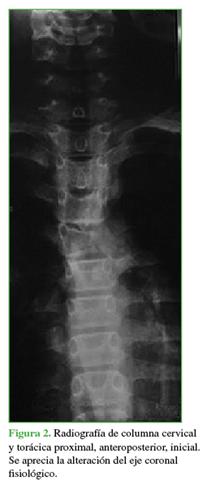

En la radiografía inicial de frente, se observó una alteración en el eje coronal fisiológico (Figura 2).